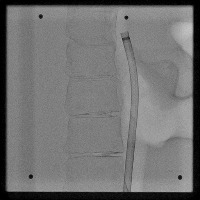

Healthcare Monitoring: "Cath" can be used in a real-time monitoring system within healthcare facilities. It can identify the position and type of a catheter tip in an x-ray, greatly helping healthcare professionals to assess the situation of patients having a lumbar puncture or spinal catheter implantation.

Medical Training: This model can be an excellent tool in medical education. It can help train medical students and residents to identify and locate different types of catheter tips in x-ray images. This may improve their diagnostic skills and speed.

Medical Diagnosis: "Cath" can be used in the diagnosis of possible complications associated with catheter placements. Early detection of catheter displacement can prevent further complications.